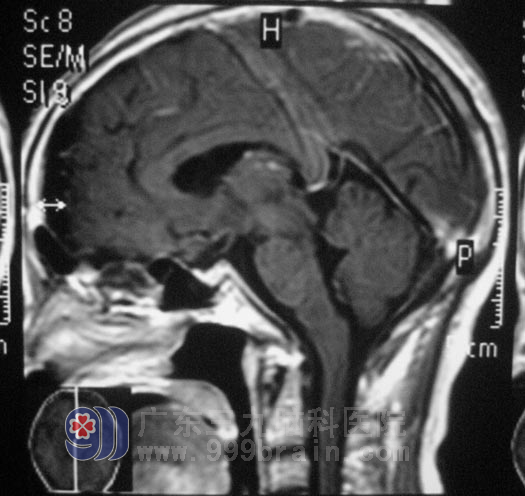

在广东三九脑科医院综合神经外科查体:左眼视力为0.4,右侧为0.6;肝内胆管结石。鲁明主任告诉黄女士的家人:麻醉过程中出现过敏的现象非常罕见,黄女士的过敏表现严重,手术风险高。10月14日,应家属要求,在全麻下行经左侧眉弓锁孔入路鞍上区颅咽管瘤部分切除+OMMAYA囊植入术,术中密切监测,没有出现过敏反应,手术顺利结束,术后黄女士很快清醒,自诉左侧视力明显较术前好转。现在黄女士除了左侧眉弓处有一几厘米长的伤口外,和正常人无异,已办理出院手续。

▲术后MR